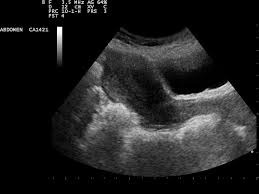

복부 초음파는 초음파(ultrasound)를 이용해 복부 내 장기들의 상태를 확인하는 비침습적 검사 방법입니다. 방사선을 사용하지 않아 인체에 해롭지 않고, 고통 없이 실시간으로 복부 장기들을 관찰할 수 있다는 점에서 가장 기본적이면서도 효과적인 진단도구로 평가받습니다.

초음파 탐촉자(Probe)에서 발생한 고주파 음파가 인체 내부 장기에 부딪혀 반사되며, 복부 초음파로 알 수 있는 것은 바로 이 반사파를 영상화해 간, 담낭, 췌장, 비장, 신장(콩팥), 방광, 대동맥, 림프절 등의 상태를 분석하게 됩니다.